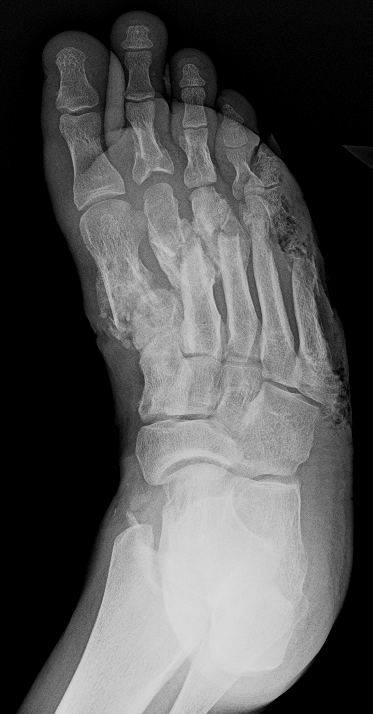

What’s the Diagnosis? Gepost op 17 december 201717 december 2017 door netwerkvsseh What’s the Diagnosis? @emdaily.cooperhealth.org Dit delen: Delen op X (Opent in een nieuw venster) X Share op Facebook (Opent in een nieuw venster) Facebook Delen op LinkedIn (Opent in een nieuw venster) LinkedIn E-mail een link naar een vriend (Opent in een nieuw venster) E-mail Afdrukken (Opent in een nieuw venster) Print Vind-ik-leuk Aan het laden... Gerelateerd